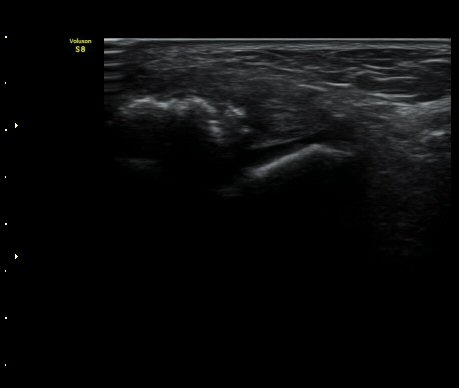

3ÁÖ ÈÄ ÃßÀû°Ë»ç»ó °üÀý³» ºÎÁ¾ÀÌ ¼Ò½ÇµÇ°í(±×¸² 4). Àü°Å°ñºñ°ñÀδëÀÇ Àú¿¡ÄÚ ºÎÁ¾ÀÌ

°¨¼ÒÇÏ°í °ß¿­°ñÀý °ñÆíÀº ºñ°ñ °¡±îÀÌ À§Ä¡Çϰí ÀÖ´Ù(±×¸² 5, 6).

±×¸²4) 3ÁÖ ÈÄ ÃßÀû°Ë»ç

±×¸²5) 3ÁÖ ÈÄ ÃßÀû°Ë»ç